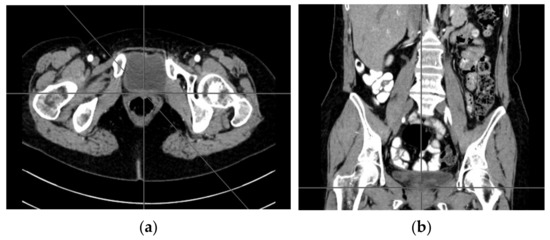

A computer tomography of the abdomen and pelvis was also performed every 3 months for the possible detection of ovarian cancer recurrence. No CT changes suggestive of recurrence were observed in the patient during the treatment. There are illustrates scans on the same section from CT performed at the beginning of PARP inhibitor treatment (Figure 2) and before 48 cycle of olaparib chemotherapy (Figure 3).

Figure 2.

(a–d) CT scans performed at the beginning of olaparib treatment.